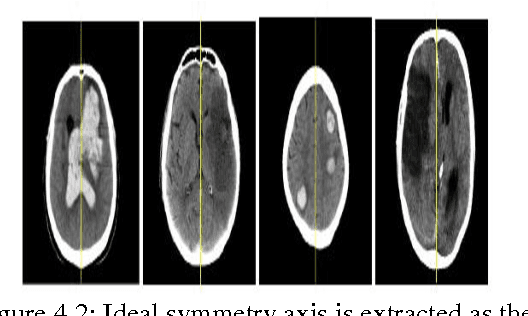

Abstract:Advances in computing technology have allowed researchers across many fields of endeavor to collect and maintain vast amounts of observational statistical data such as clinical data,biological patient data,data regarding access of web sites,financial data,and the like.Brain Magnetic Resonance Imaging(MRI)segmentation is a complex problem in the field of medical imaging despite various presented methods.MR image of human brain can be divided into several sub regions especially soft tissues such as gray matter,white matter and cerebrospinal fluid.Although edge information is the main clue in image segmentation,it can not get a better result in analysis the content of images without combining other information.The segmentation of brain tissue in the magnetic resonance imaging(MRI)is very important for detecting the existence and outlines of tumors.In this paper,an algorithm about segmentation based on the symmetry character of brain MRI image is presented.Our goal is to detect the position and boundary of tumors automatically.Experiments were conducted on real pictures,and the results show that the algorithm is flexible and convenient.